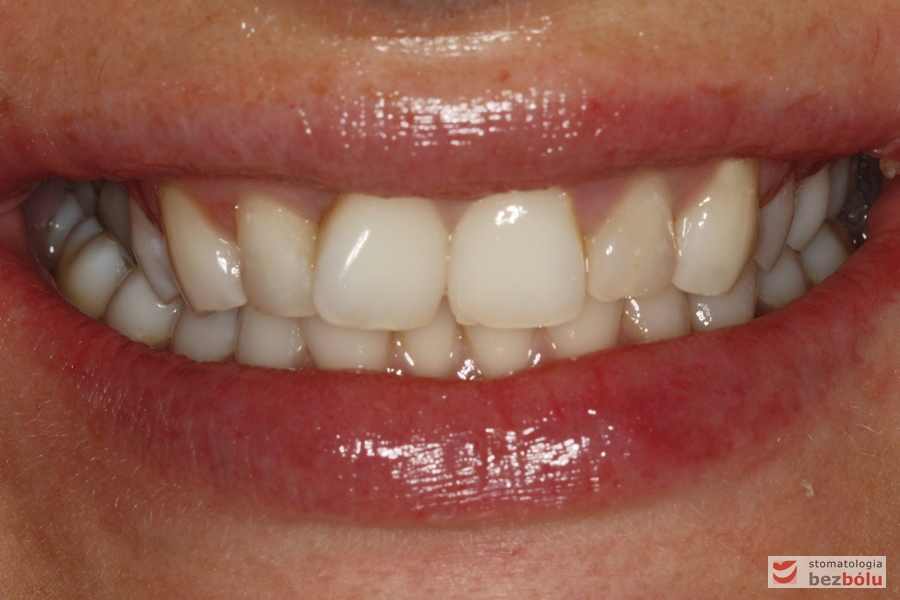

Analiza uśmiechu po zacementowaniu pracy ostatecznej - en face

Analiza uśmiechu po zacementowaniu pracy ostatecznej – en face

Pozytywna przemiana uśmiechu - obraz kliniczny przed terapią stomatologiczną

Pozytywna przemiana uśmiechu – obraz kliniczny przed terapią stomatologiczną

Pozytywna przemiana uśmiechu - obraz kliniczny po terapii stomatologicznej

Pozytywna przemiana uśmiechu – obraz kliniczny po terapii stomatologicznej